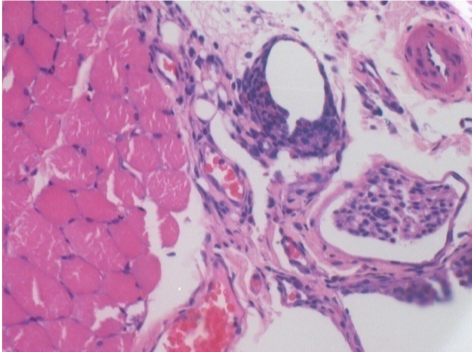

Через 10 днів після ін'єкції Ендопіл 0,1 мл в правий претибіальний м'яз.

Тут можна побачити утворення вакуолей, які оточені лімфоцитами. Вакуолі відрізняються від некрозу тканини. Присутність лімфоцитів пов'язана з проникністю клітинних мембран.